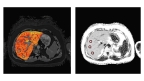

LiverMultiScan images of a liver with high cT1 values and high PDFF (Photo: Business Wire)

These funds have been awarded under the Drug Development Tool Research Grant (U01). The study will qualify the imaging markers cT1 and PDFF as drug development tools in non-alcoholic steatohepatitis (NASH); initially as diagnostic screening biomarkers to identify patients for inclusion in NASH clinical trials, then as pharmacodynamic efficacy biomarkers to detect clinically meaningful change, with the ultimate objective being approval as non-invasive surrogate endpoints. LiverMultiScan will help identify patients for NASH clinical trials.

In discriminating healthy volunteers and patients with no fibrosis on liver biopsy from those with any degree of fibrosis (Ishak ⩾ F1), cT1 had a sensitivity of 86% and a specificity of 93% at a threshold of 800ms. (Journal of Hepatology, 2014, 60(1), 69 – 77).